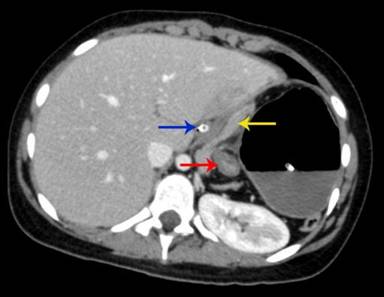

Laboratory investigations showed the patient to be anaemic (Hb 9 gm%) with leucocytosis (16,000/cubic mm) and a predominance of polymorphonuclear cells (80%). Scanogram revealed a dilated stomach with inverse orientation as evidenced by the position of the Ryle’s tube (Figure 1). A screening abdominal ultrasound failed to demonstrate the spleen in the left hypochondrium. The spleen was present in the umbilical region and extended into the left lumbar region. The bowel loops occupied the left upper quadrant. A contrast enhanced computed tomography (CECT scan) of the chest and abdomen was performed. It depicted a grossly distended stomach with the fundus lying in the left hemi-thorax and an air-fluid level within (Figure 2). The pylorus lay close but a little above the gastro-oesophageal junction, a finding consistent with gastric volvulus (Figure 3). There were no accompanying signs of gastric infarction. An enlarged spleen was visualised occupying the umbilical and the left lumbar region, extending along the undersurface of the left lobe of the liver and reaching below the lower pole of the left kidney (Figures 4, 5). The splenic pedicle had undergone torsion with consequent volvulus of pancreatic tissue. The splenic parenchyma however, had a homogenous attenuation, thus excluding any splenic ischemia. The pancreas was seen compressed between the stomach and the spleen (Figures 3, 5). A diagnosis of pancreatic volvulus due to torsion of wandering spleen, diaphragmatic hernia with an intra-thoracic gastric volvulus and resultant gastric outlet obstruction was thus established.

Figure 3. Axial CT scan abdomen shows the gastro-esophageal junction with Ryle’s tube in situ (blue arrow) and the pylorus (red arrow) with compression of the pancreatic tissue (yellow arrow). |

Figure 4. Axial CT scan abdomen shows an enlarged wandering spleen (red arrow), extending from the undersurface of the left lobe of the liver (a.) extending medially to the distended stomach up to the lower pole of the left kidney (b.). |

Figure 5. CECT abdomen, coronal reformatted images, show the presence of the wandering spleen (red arrows) and the pancreatic volvulus (yellow arrows). |